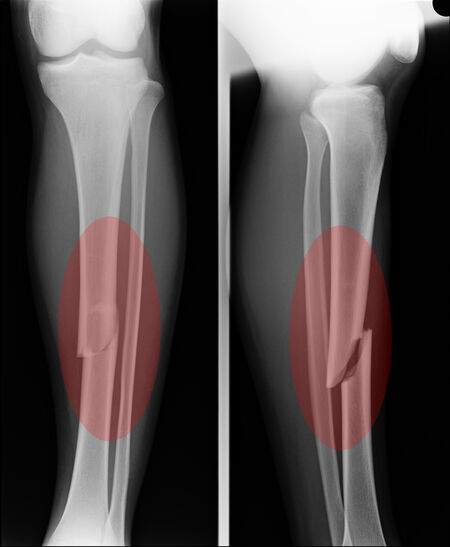

Traumatic Fracture

Trauma and Fractures | OASIS Orthopaedics Melbourne Traumatic Injury & Fracture Treatment - My Toronto Physio Traumatic Spine Fracture - Goodman Campbell All Types of Fractures & Trauma - Dr. Prajaktam Lende's Niva Ortho Care | Orthopedic Surgeon In Nagpur | Orthopedic Doctor in Nagpur | Traumatic Fracture